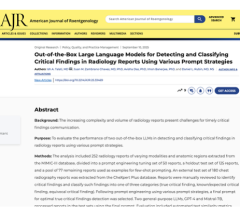

Sept. 10, 2025 — According to ARRS’ American Journal of Roentgenology (AJR), general-purpose large language models (LLMs ...